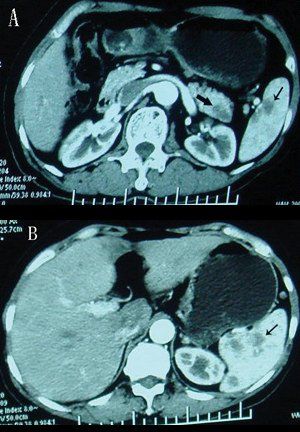

The presence of an abdominal blood clot may be a sign of cancer and may also be associated with poor survival for patients with pancreatic or liver cancers.